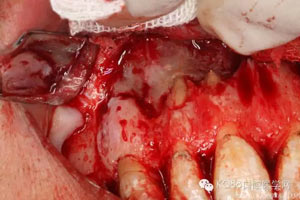

圖4.翻瓣、去除覆蓋在囊腫表面骨質(zhì),暴露出囊壁。